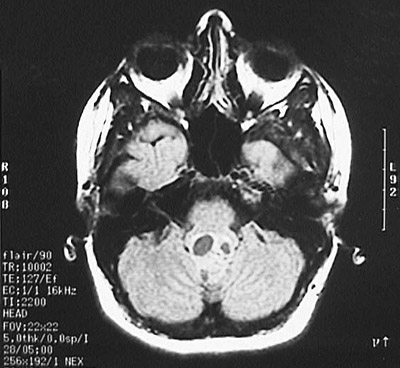

This computed tomographic (CT) imaging scan demonstrates a discrete mass filling the fourth ventricle. This is an ependymoma, the most common neoplasm at this site, and a common place for an ependymoma. There is some cystic change in this ependymoma.